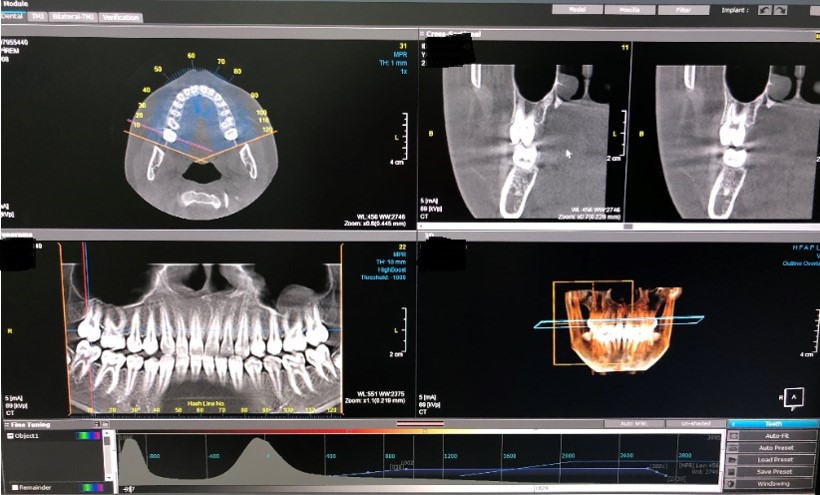

Dental tomografi x-ışını kullanılarak incelenmek istenilen bölgenin kesitsel görüntüsünün elde edildiği bir radyolojik yöntemdir. Daha net, ayrıntılı ve volümetrik görüntüleme olanağı sağlar. Klasik diş röntgeninden en önemli farkı dental tomografinin 3 boyutlu görüntü sağlamasıdır. Bu da uzunluk, genişlik ve derinlik de dahil üç boyutlu görüntüleme, tüm dişlerin, çene kemiğinin ve hava yolunun etrafını görebilme imkanı verir. Dental tomografi, çeşitli diş hastalıklarının teşhis ve tedavisini planlamada yol göstericidir. Ayrıca çene eklemini (temporomandibular eklemi) değerlendirmeye yönelik çekimler de yapılabilmektedir.

Daha iyi görüntü kalitesi ve daha yüksek doğruluk ile üç boyutlu bakış imkanı sağlar. Kemik ve yumuşak dokuların net görüntüsü elde edilir. Geleneksel diş röntgenlerinden farklı olarak, Dental BT ile hem kemik hem de yumuşak doku kolayca taranabilir. Dental BT daha doğru teşhis ve hassas bir tedavi planı oluşturabilme şansı sağlar. Hastanın ağzının ve dişlerinin kapsamlı bir görünümü elde edilir. Her tarama, diş hekiminin kontrastıyla oynayarak görüntüleri değiştirebileceği kesitler ve farklı açılardan incelenebilen hacimsel data üretir. Dental tomografi invazif olmayan ve ağrısız bir çözüm sunar.